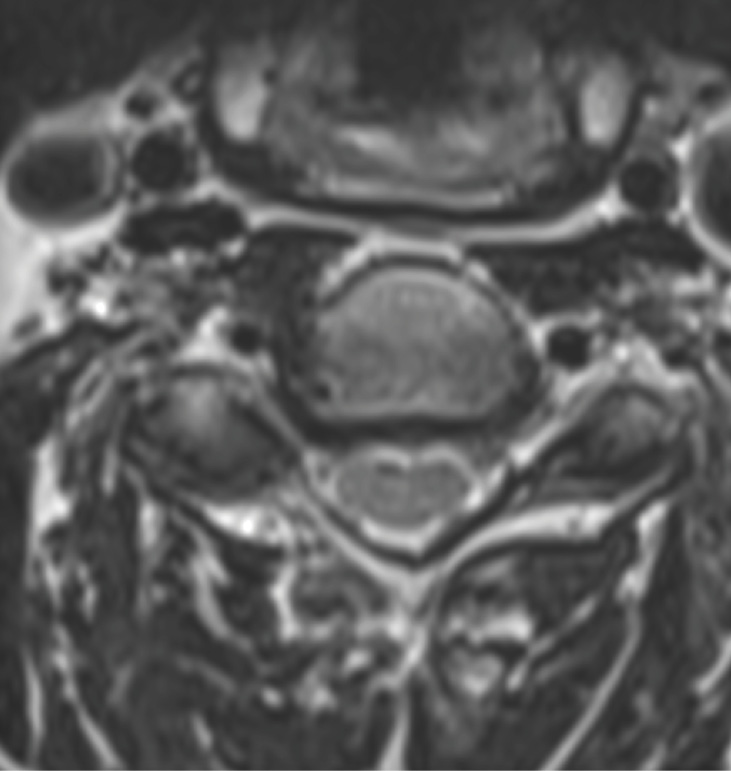

Pre-op MRI demonstrates partial disc height collapse and foraminal stenosis at C5-6 and C6-7.